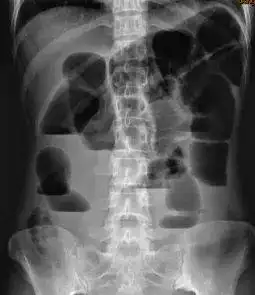

「案例分析」为何年纪轻轻也会腰痛?

原创在x光片上如何辨别骨盆前倾与后倾